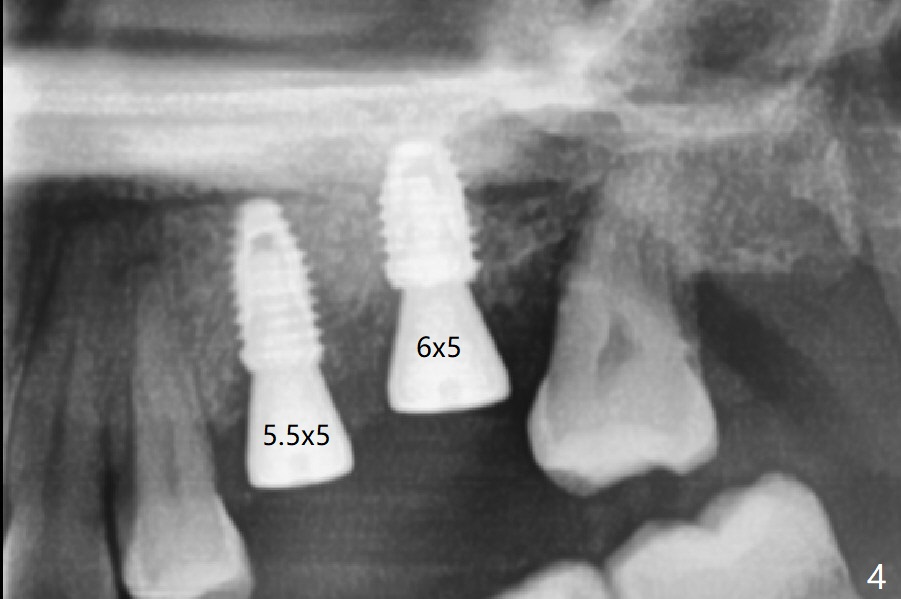

After placement of a 4.5x8.5 mm implant at #13, a vertical anchor pin is used, which is helpful for #14 osteotomy (Fig.1-3). One hand is free. Sinus lift with 2.8 mm reamer is not efficient, since it is difficult to feel stopper. A 5x7.3 mm implant has to be removed from the site of #14 for use of Magic Expanders from 3.0 to 4.3 mm at the depth of 13 mm (gingival level). Autogenous bone harvested from osteotomy is used for sinus lift. It appears that the implants are placed deep; healing abutments with 5 mm cuff are placed (Fig.4 (extraoral bitewing)).